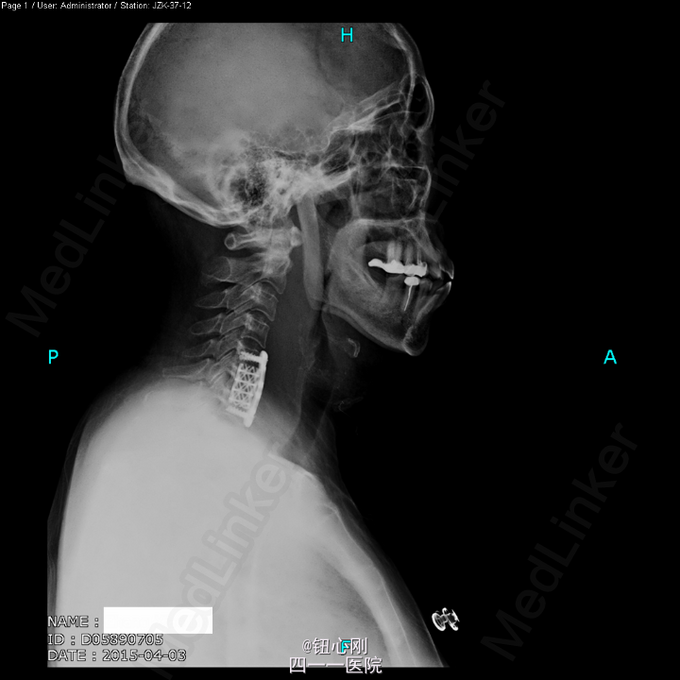

体检未见明显阳性体征。 辅助检查:血沉68mm/h,神经元特异性烯醇化酶23ug/l,余肿瘤指标正常。三大常规、肝肾功、电解质正常。 颈椎MRI、腰椎MRI及PET-CT扫描见图。

术前诊断:多椎体病变待查(转移瘤?) 诊断依据:老年女性,出现颈腰部疼痛,MRI及PET-CT扫描提示椎体多节段病变,以转移瘤可能性为大,同时血沉升高。 处理:2015-03-31在全麻下行颈6椎体病变前路次全切+钢板钛网植骨融合内固定术。术中所见:颈6椎体骨质疏松,部分硬化,未见鱼肉样组织。术后切除骨质送病理检查。 病理报告:骨小梁稀疏,其间有纤维组织,同时可见硬化死骨。 术后诊断:颈6椎体骨质疏松性骨坏死。